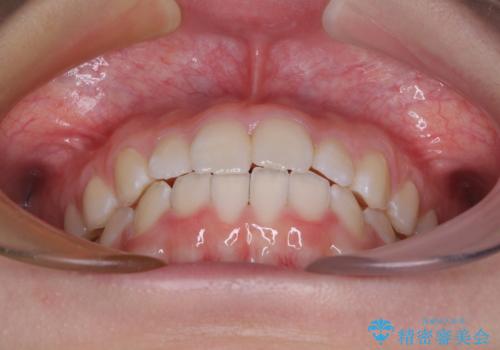

- 前歯のデコボコを気にして来院された高校生の患者様です。

捻れた前歯が前方に飛び出している点も気になっており、目立たない装置を希望されたため、インビザラインを用いて矯正治療を行うこととしました。

上下ともに少し捻れが残っていたため、治療の継続を提案しましたが、本人も親御さんも満足とのことで、治療を終えました。

捻れの改善により突出感も改善されました。